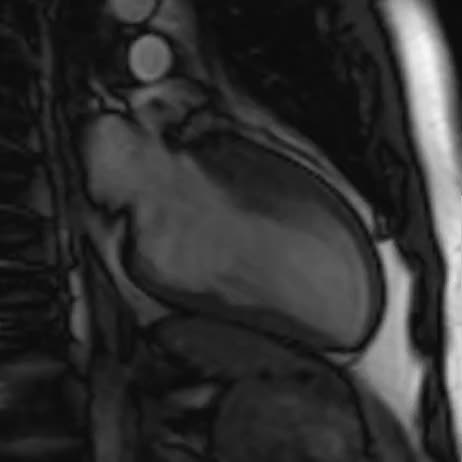

Imaging cardiovascolare 2020. Disfunzione ventricolare sinistra post-ischemica. Lo studio del rimodellamento ventricolare ai tempi della RM.